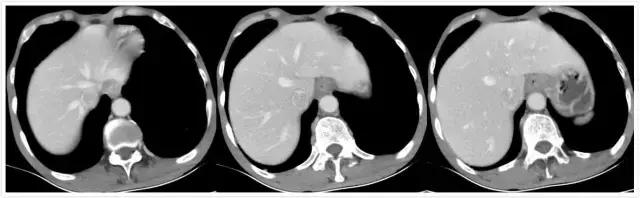

患者男性68岁,主因消瘦2个月,腹部不适入院就诊。详细检查报告及影像资料如下:

中晚期胃底贲门腺癌,诊断已明确。治疗方案有